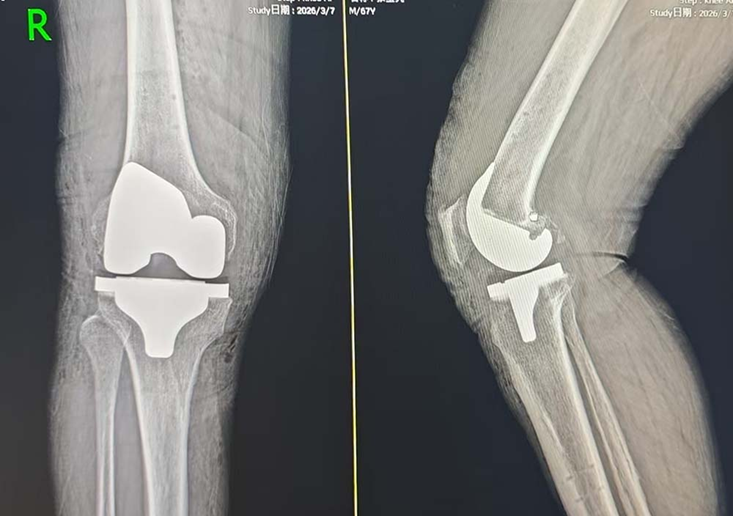

2026年2月、4月,张大爷分两次在该院接受了Mako机器人辅助下的左膝、右膝全膝关节置换手术。术前Mako机器人依据张大爷的检查报告,生成符合生理结构的3D虚拟模型,制定详细的术前规划,术中机器人经过精确计算,辅助医生完成截骨、安装假体等手术操作,精准度至0.1毫米,有效减少对患者的创伤,让手术更安全、更精准。